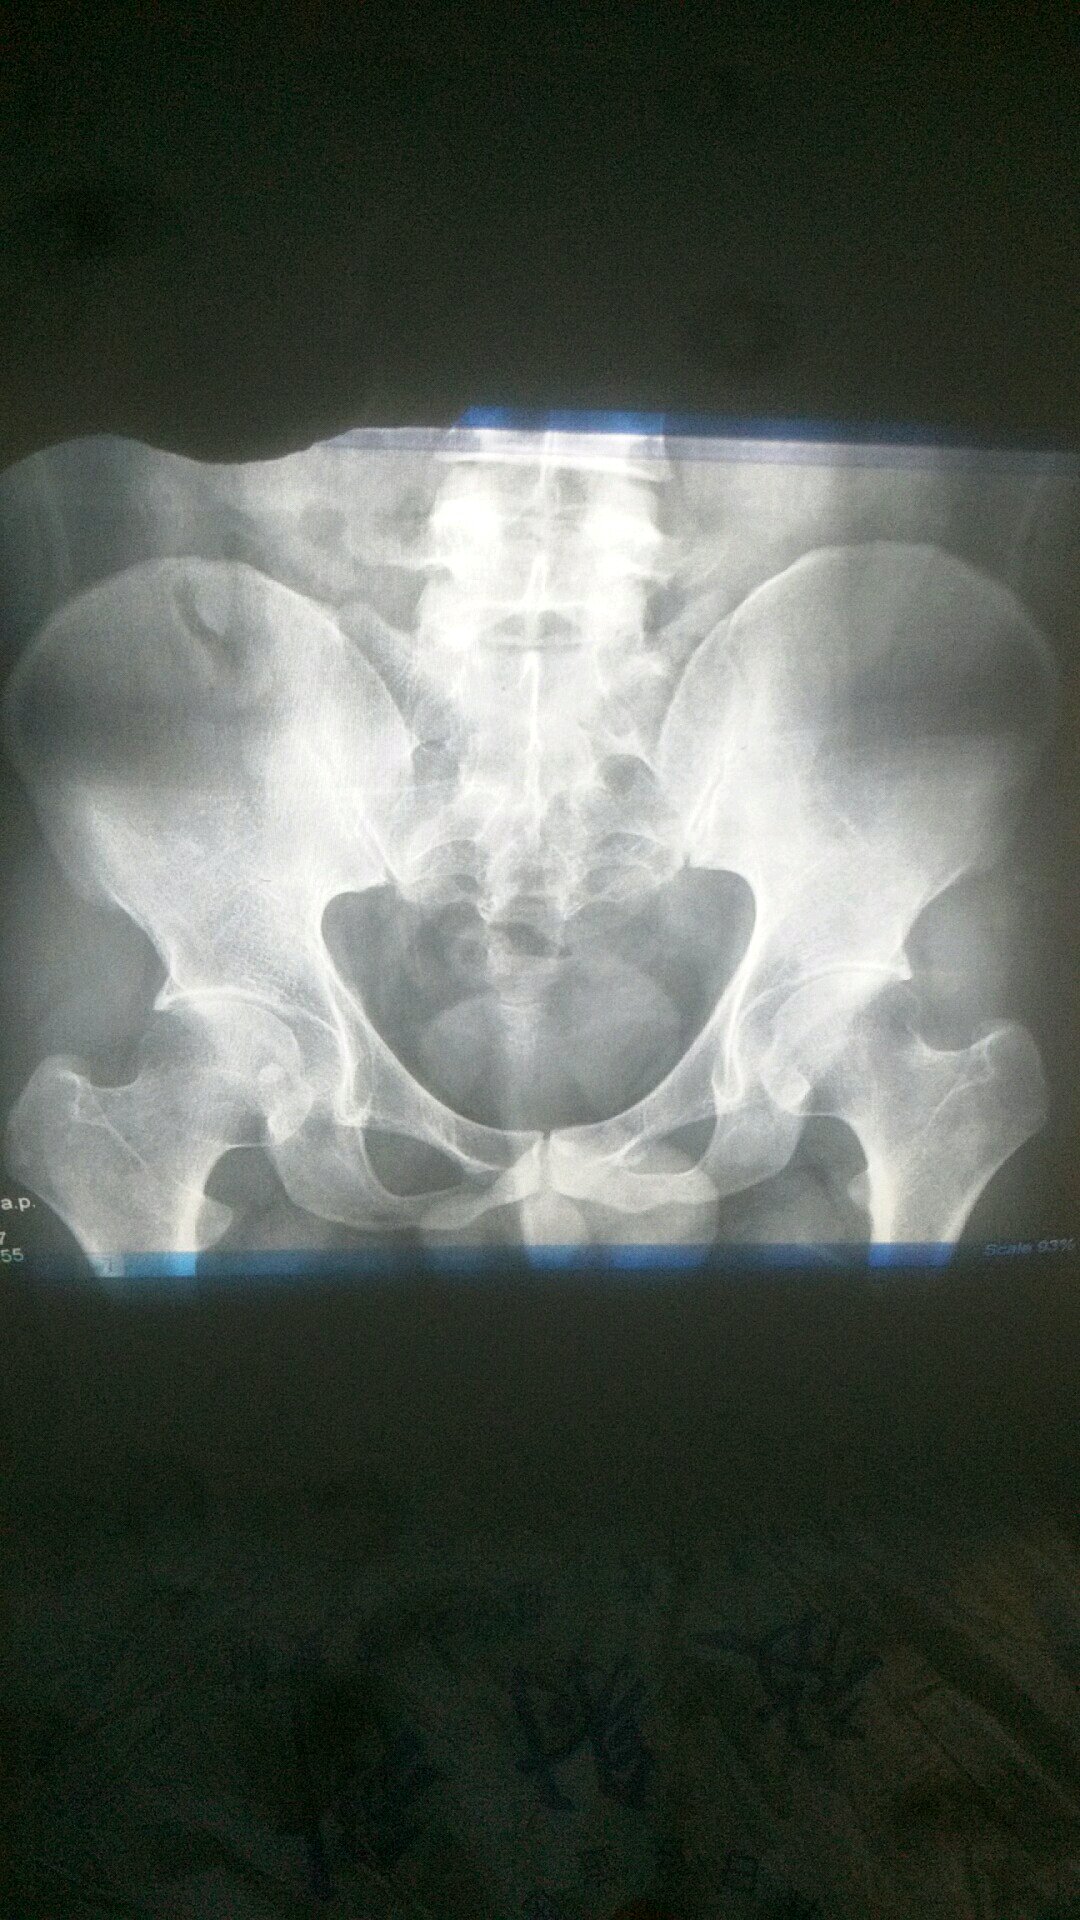

两次DR的片子,第一张我今天晚上拍的,报告中说右股骨颈骨折,

两次DR的片子,第一张我今天晚上拍的,报告中说右股骨颈骨折,大夫说不是骨折,报告中写的骨折,想问下大家如果真的是骨折了,可以不打钉子吗?